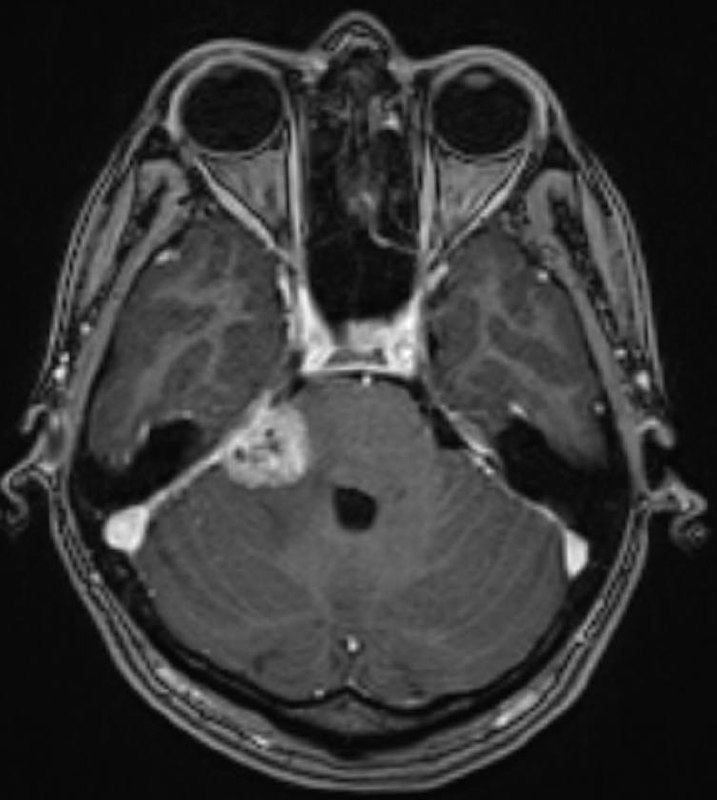

Анапластическая менингиома намета мозжечка справа с оболочечной спинальной диссеминацией у пациента 36 лет.